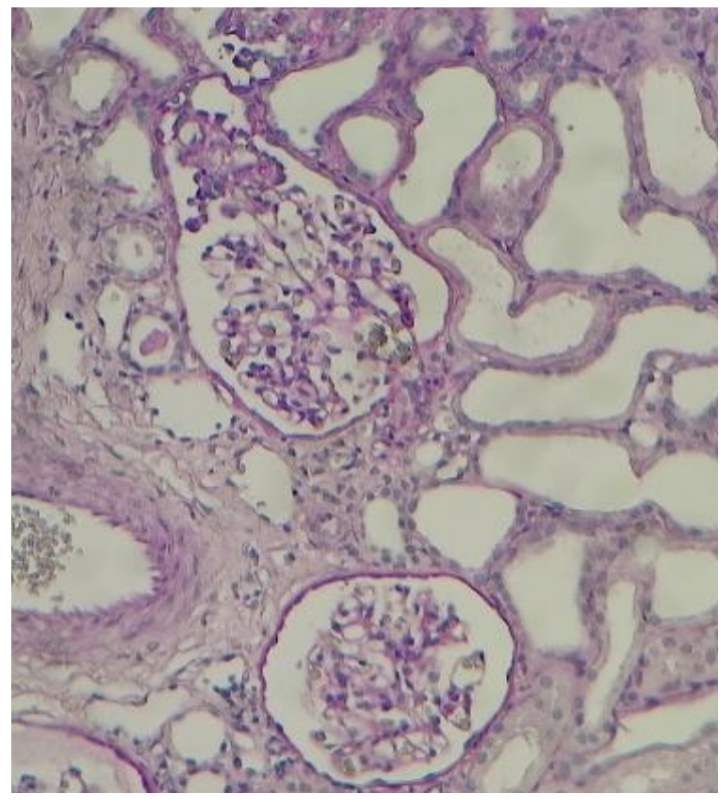

El paciente cursa con empeoramiento de la función renal y ausencia de respuesta al manejo diurético, por lo que ingresa a hemodiálisis de soporte. Se realizó toracocentesis evacuatoria de 900 ml, con líquido transparente característico de trasudado; también paracentesis diagnóstica y evacuatoria de 2000 ml, de líquido claro con característica de trasudado y GASA 0.8, que indica como causa probable de la ascitis al SN. Se realizó biopsia renal (figura 2): podocitopatía, glomerulopatía colapsante. Se inicia tratamiento con corticoterapia, evidenciándose mejoría de la función renal, por lo que se suspende hemodiálisis. Paciente es dado de alta para seguimiento ambulatorio, pero con persistencia de ascitis.